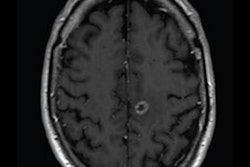

How to determine whether or not a cerebral aneurysm clip is ferromagnetic when the hospital of implantation is unknown in the Netherlands. Tables courtesy of Dr. Mark B.M. Hofman and colleagues and ISMRM.Risks assessment for the clips was performed based on the standard risks for metallic implants in the MRI. The risk of displacement and rotation of the implant due to the presence of the static magnetic field and the spatial gradient of this field is the main risk for ferromagnetic clips. For nonferromagnetic models, the risk is negligible.

- Artifact in the MRI image: for ferromagnetic clips up to 4 cm, otherwise typically < 1 cm.